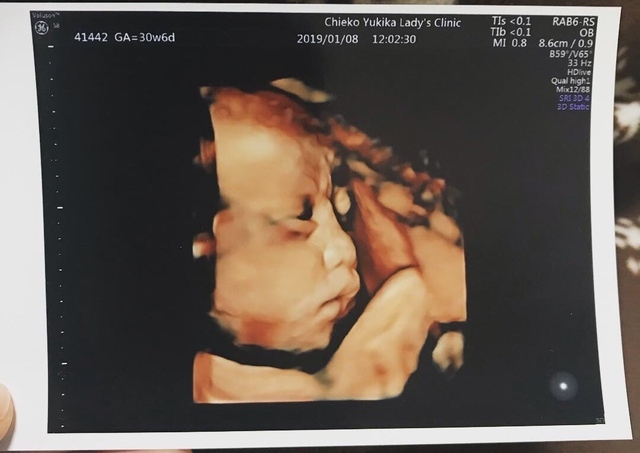

30週6日(30w6d・男の子)|あやたまご♪ さん(25歳)

エコー写真撮影時のエピソード:

初めて4Dエコーを撮った時のエコー写真です。どんな顔かドキドキしながら4Dエコーをした覚えがあります。24週目くらいから4Dエコーを撮っていましたが、1回目は後ろを向いていたので撮れず、2回目は手で顔を隠していたので撮れず…。

3度目の正直でやっとちゃんと顔が見えました。主人に顔がそっくりで笑ってしまったのを覚えています。主人は、そうかな~!?と言っていましたが、本当に似ています(笑)今でも大切な思い出の写真です。